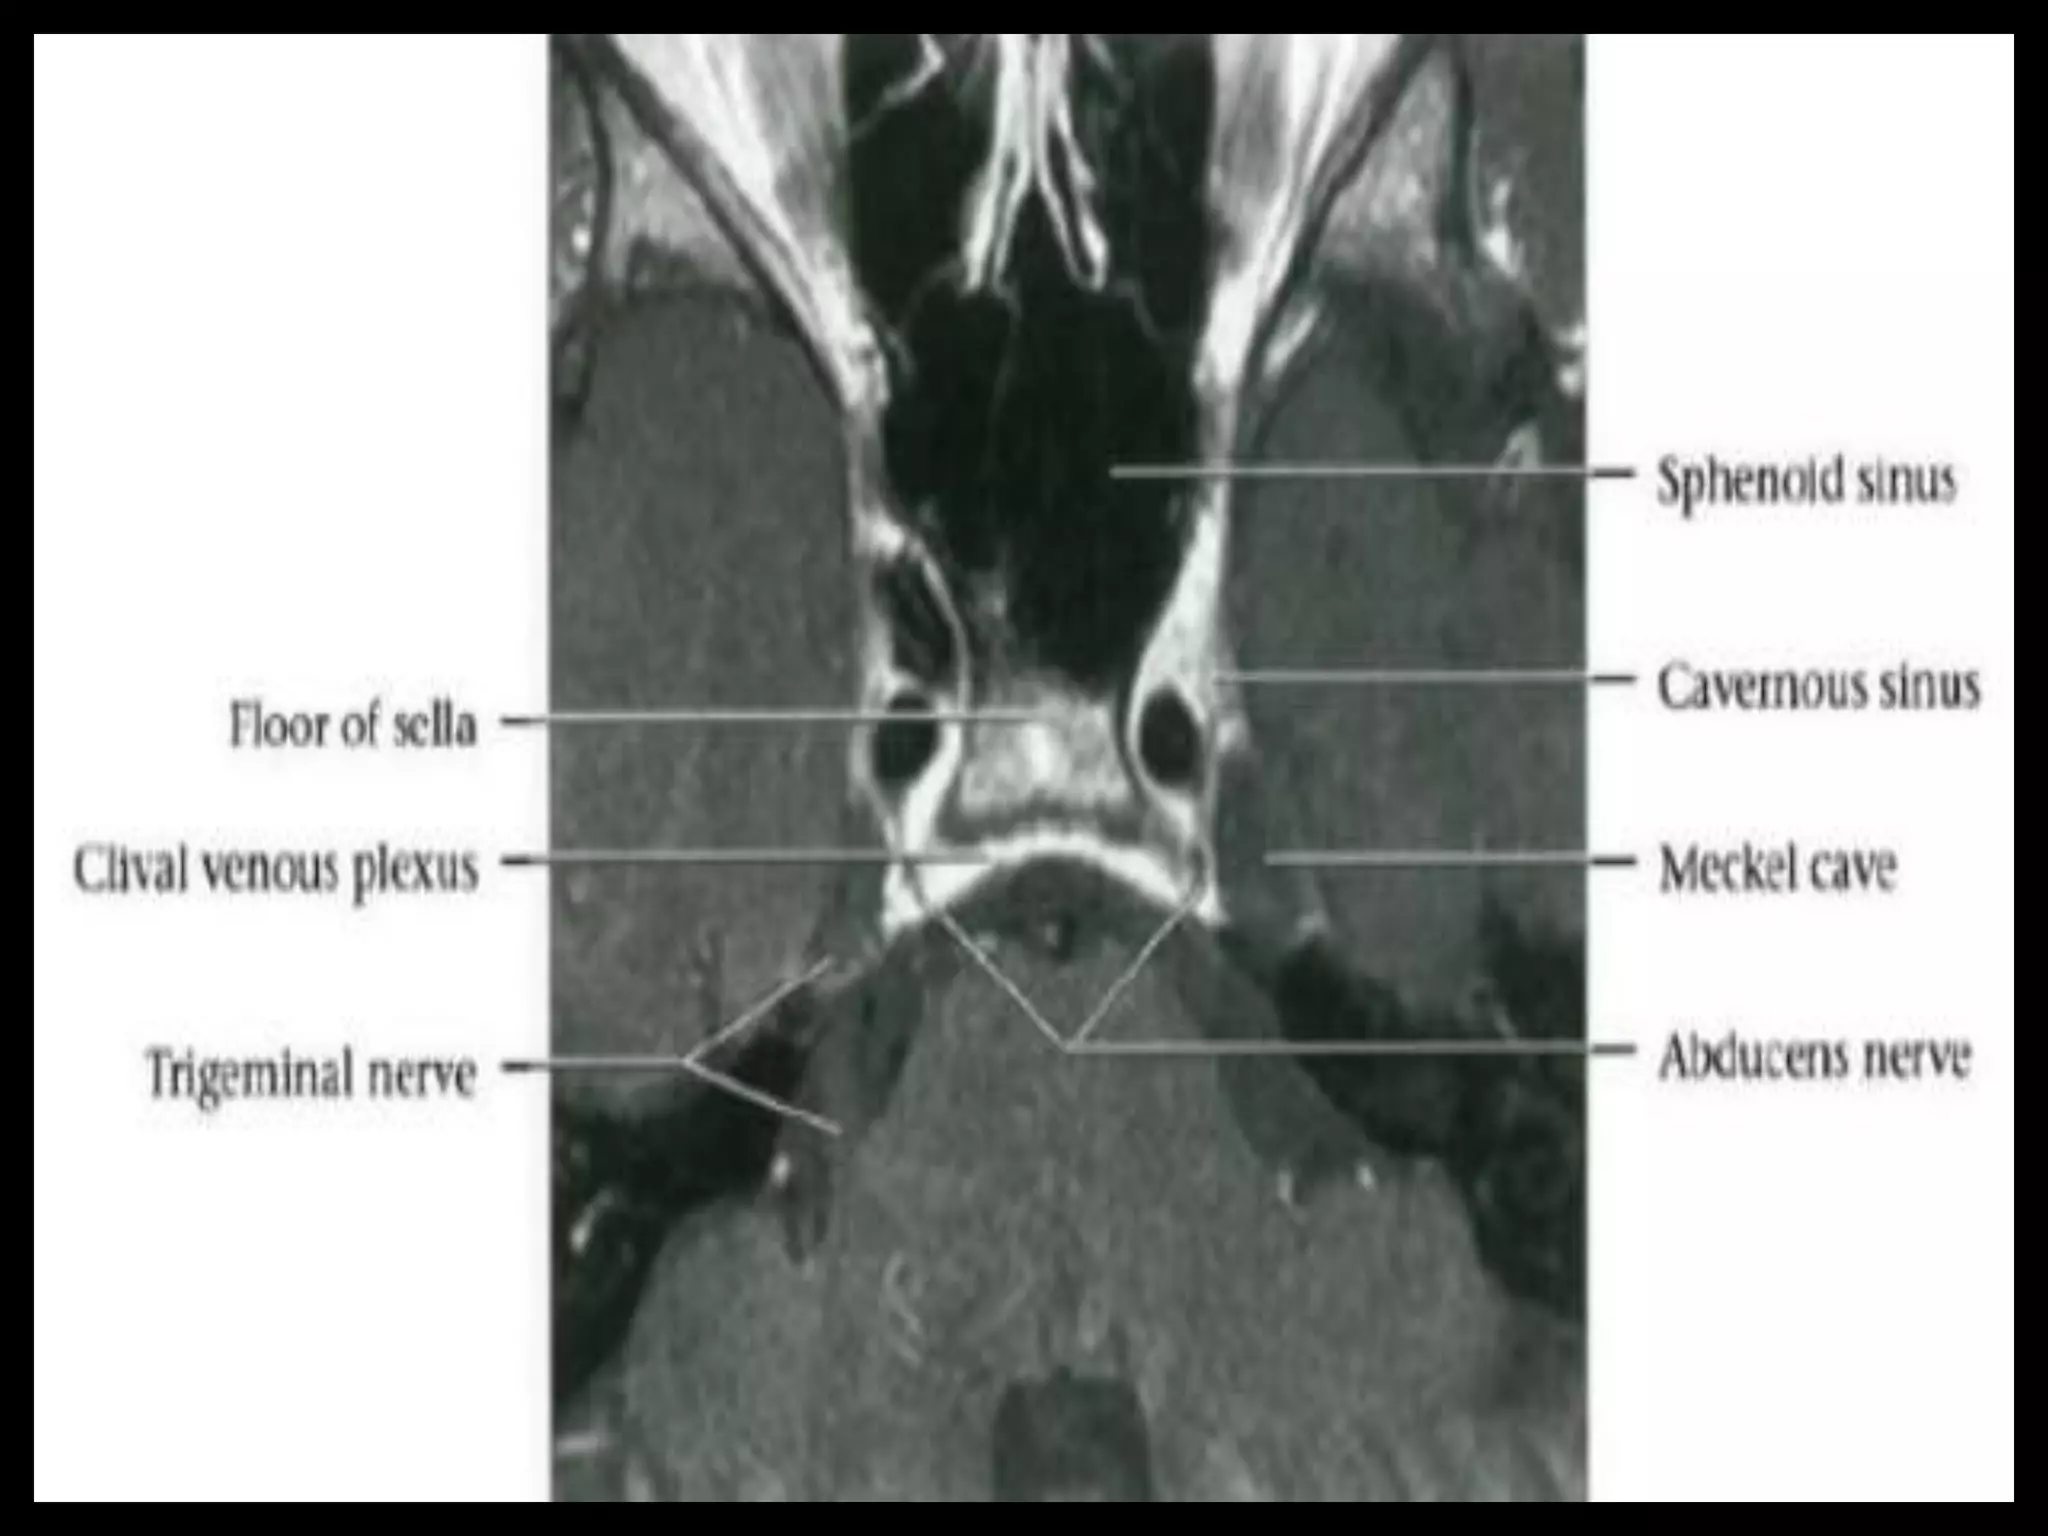

Sectional Anatomy: NormalAxial CT and MRI Anatomy. On CT and MR scans, the brain has been briefly viewed in infratentorial and supratentorial sections, as described below. CT scans are performed with a 15- to 20-degree angulation to the canthomeatal line at 8-mm increments. MRI scans are generally obtained parallel to the AC-PC line in the axial plane with 6-mm slice thickness. Using the sagittal view, the coronal sections are acquired parallel to the brain stem, and the sagittal sections are obtained perpendicular to the axial section. On MRI studies, cranial nerves IX and X can be demonstrated at this level because they emerge from the postolivary sulcus. The posterior aspect of the cerebellar hemispheres is outlined by the inferior portion of the cisterna magna.